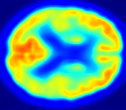

In Fig. 4, the attention maps of the U-PET are shown for multiple examples. On the one hand, the attention map of the skip connection (AttMap skip) highlights details of the brain structure, which is in agreement with the assumption that the network has to transform the specific structures of the MRI scan into the PET modality. On the other hand, the attention gates used for the classification task rather focus on more specific regions. One can observe a trend that the attention maps used for classification tend to highlight regions which have a low uptake in the PET. Since areas with a lower uptake in the PET correspond to areas with lower functional activity (hypometabolism), this focus area of the network seems reasonable with respect to the classification task.